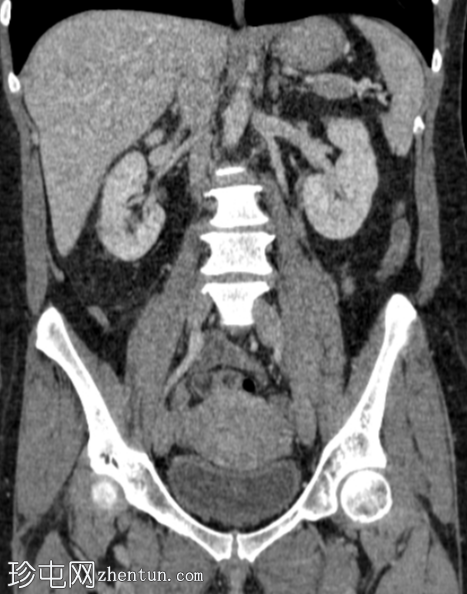

冠状位增强扫描(门静脉期)

右肾轴位和冠状位图像均显示肾实质下部低强化区域,伴肾周脂肪间隙模糊,符合急性肾盂肾炎的

影像

学表现。

膀胱壁轻度环周增厚及强化,可能为轻度膀胱炎。

左侧黄体囊肿。